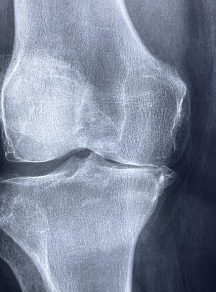

무릎 연골 손상 증상 원인 치료방법 등 무릎 연골과 관련된 정보를 알아보도록 하겠습니다. 무릎 연골은 무릎 관절의 표면을 덮고 있는 유연한 조직으로, 무릎의 움직임과 충격을 완화하는 역할을 합니다. 무릎 연골은 신체 활동, 노화 등에 의해 마모되어 손상되거나 파열될 수 있습니다. 이는 무릎 통증, 부종, 불규칙한 관절 운동 등의 증상을 일으키며, 심각한 경우 무릎 관절염으로 진행될 수도 있습니다. 무릎 연골 손상의 치료 방법에는 보존적 치료, 수술적 치료 등이 있으며, 예방적으로는 적절한 운동, 체중 관리, 안전한 스포츠 활동 등이 중요합니다. 또한, 연골이 손상된 경우 조기에 적절한 치료를 받는 것이 중요하며, 의학적 진단과 전문적인 치료가 필요합니다.

무릎 연골 손상 증상은 다양하며, 손상의 정도와 위치에 따라 다를 수 있습니다. 일반적인 증상으로는 다음과 같은 것들이 있습니다.

- 통증: 무릎 관절 주변에 생기는 통증이며, 통증은 보통 활동 중 또는 특정한 자세를 취했을 때 더욱 심해집니다. 통증은 가벼울 수도 있고, 심하거나 지속적일 수도 있습니다.

- 부종: 무릎 관절 부위에 부어오르는 증상으로, 가끔은 발열과 함께 나타납니다.

- 운동 제한: 무릎 관절을 움직일 때 마찰이나 제한을 느끼는 경우가 있습니다. 무릎을 구부리거나 똑바로 펴는 것이 어려울 수 있습니다.

- 무릎 관절 이상 소리: 삐걱거리는 소리나 으깨지는 소리 등이 들릴 수 있습니다.

- 무릎의 불안정감: 무릎이 흔들리는 느낌이나 불안정한 느낌을 주는 경우가 있습니다.

- 변형: 무릎 관절의 형태가 변형되는 경우가 있습니다. 이는 손상이 심한 경우에 나타납니다.

이와 같은 증상이 나타날 경우, 무릎 연골 손상이 의심됩니다. 무릎 연골 손상은 조기에 진단하고 치료해야 하며, 치료를 미룰 경우 보다 심각한 증상으로 이어질 수 있습니다. 따라서, 무릎 연골 손상의 증상이 있을 경우, 전문의를 찾아 진단과 치료를 받는 것이 중요합니다.